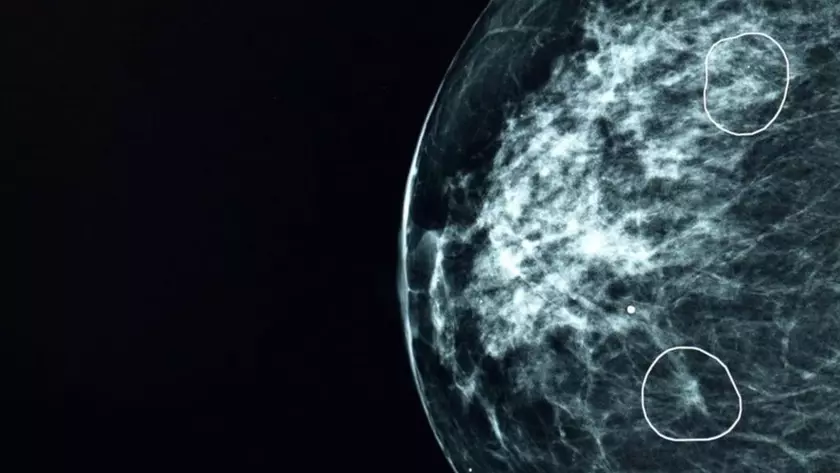

В ходе тестирования в Национальной службе здравоохранения Великобритании (NHS) инструмент искусственного интеллекта под названием Mia успешно выявил признаки рака груди у 11 женщин, которые были изначально пропущены врачами при анализе маммограмм.

При исследовании свыше 10 000 снимков грудных желез Mia правильно распознала все случаи рака, обнаруженные медиками, а также дополнительно указала на 11 пациенток с крошечными опухолями размером около 6 мм. На столь ранней стадии рак часто трудно заметить невооруженным глазом.